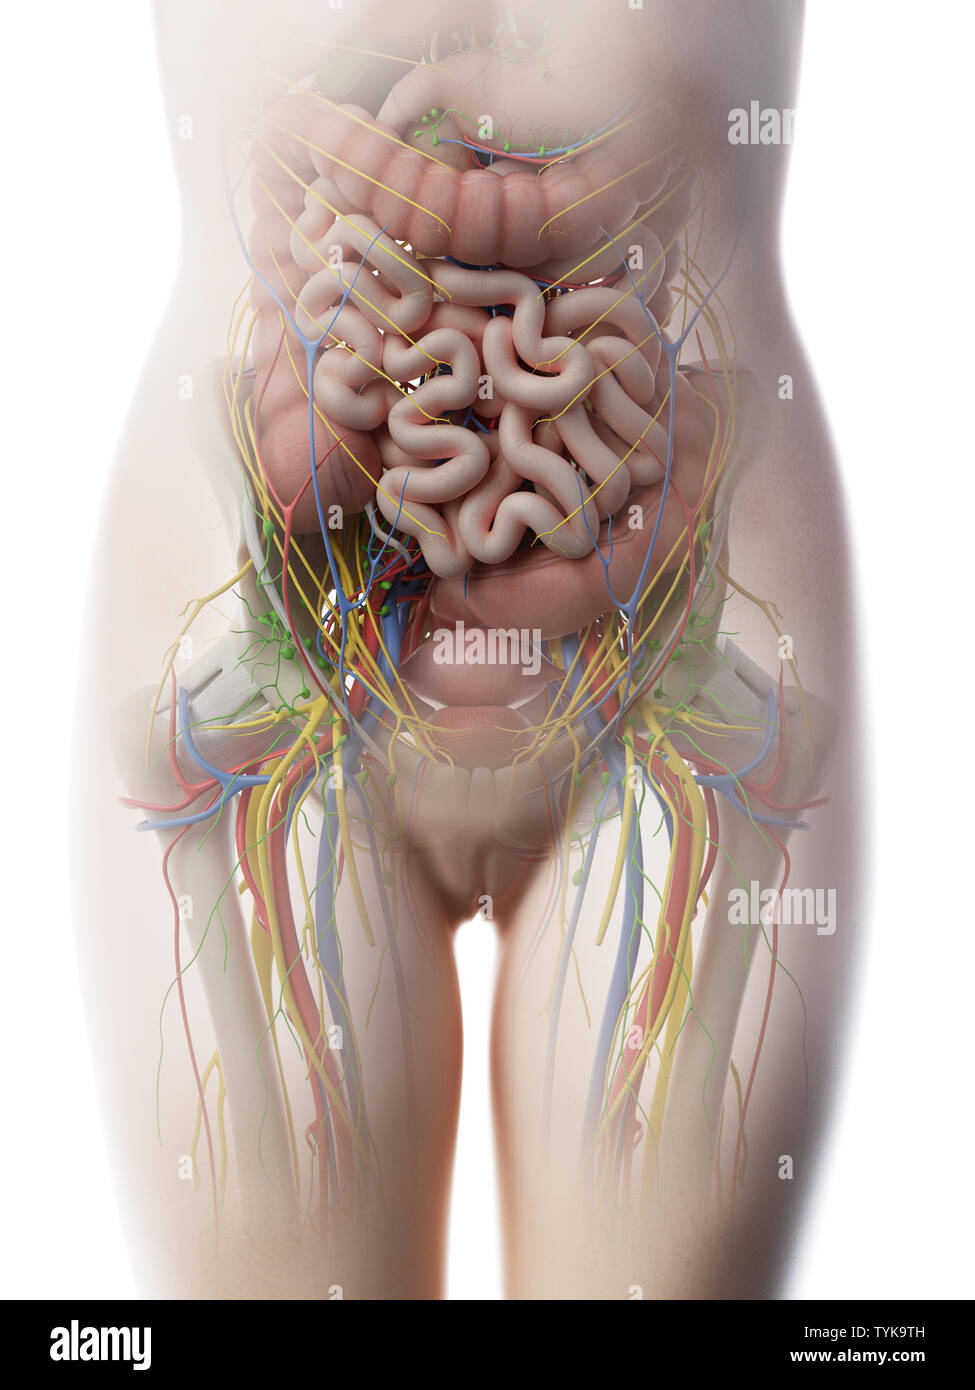

Rendu 3d illustration d'une anatomie de l'abdomen des femelles Banque D'Imageshttps://www.alamyimages.fr/image-license-details/?v=1https://www.alamyimages.fr/rendu-3d-illustration-d-une-anatomie-de-l-abdomen-des-femelles-image257965697.html

Rendu 3d illustration d'une anatomie de l'abdomen des femelles Banque D'Imageshttps://www.alamyimages.fr/image-license-details/?v=1https://www.alamyimages.fr/rendu-3d-illustration-d-une-anatomie-de-l-abdomen-des-femelles-image257965697.htmlRFTYK9TH–Rendu 3d illustration d'une anatomie de l'abdomen des femelles